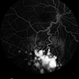

- OCTA, OCT Angiography, ultra-wide field imaging

TowardPi BMizar 400khz - Description

- Ultra-wide field OCT angiography of a 39 year-old healthy male. The photo attempts to explore retinal vasculature up to the ora serrata.